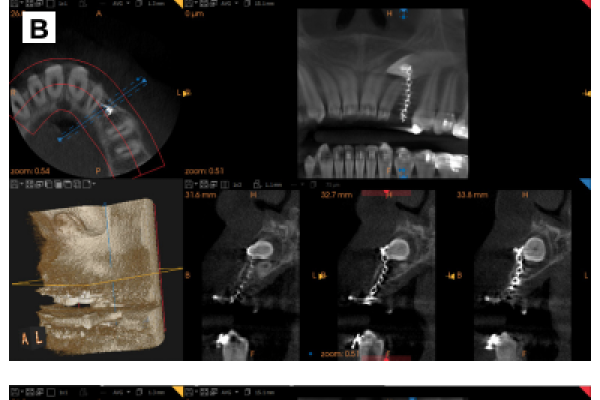

Retención de segundos molares mandibulares: evaluación mediante CBCT y consideraciones terapéuticas ante un caso clínico